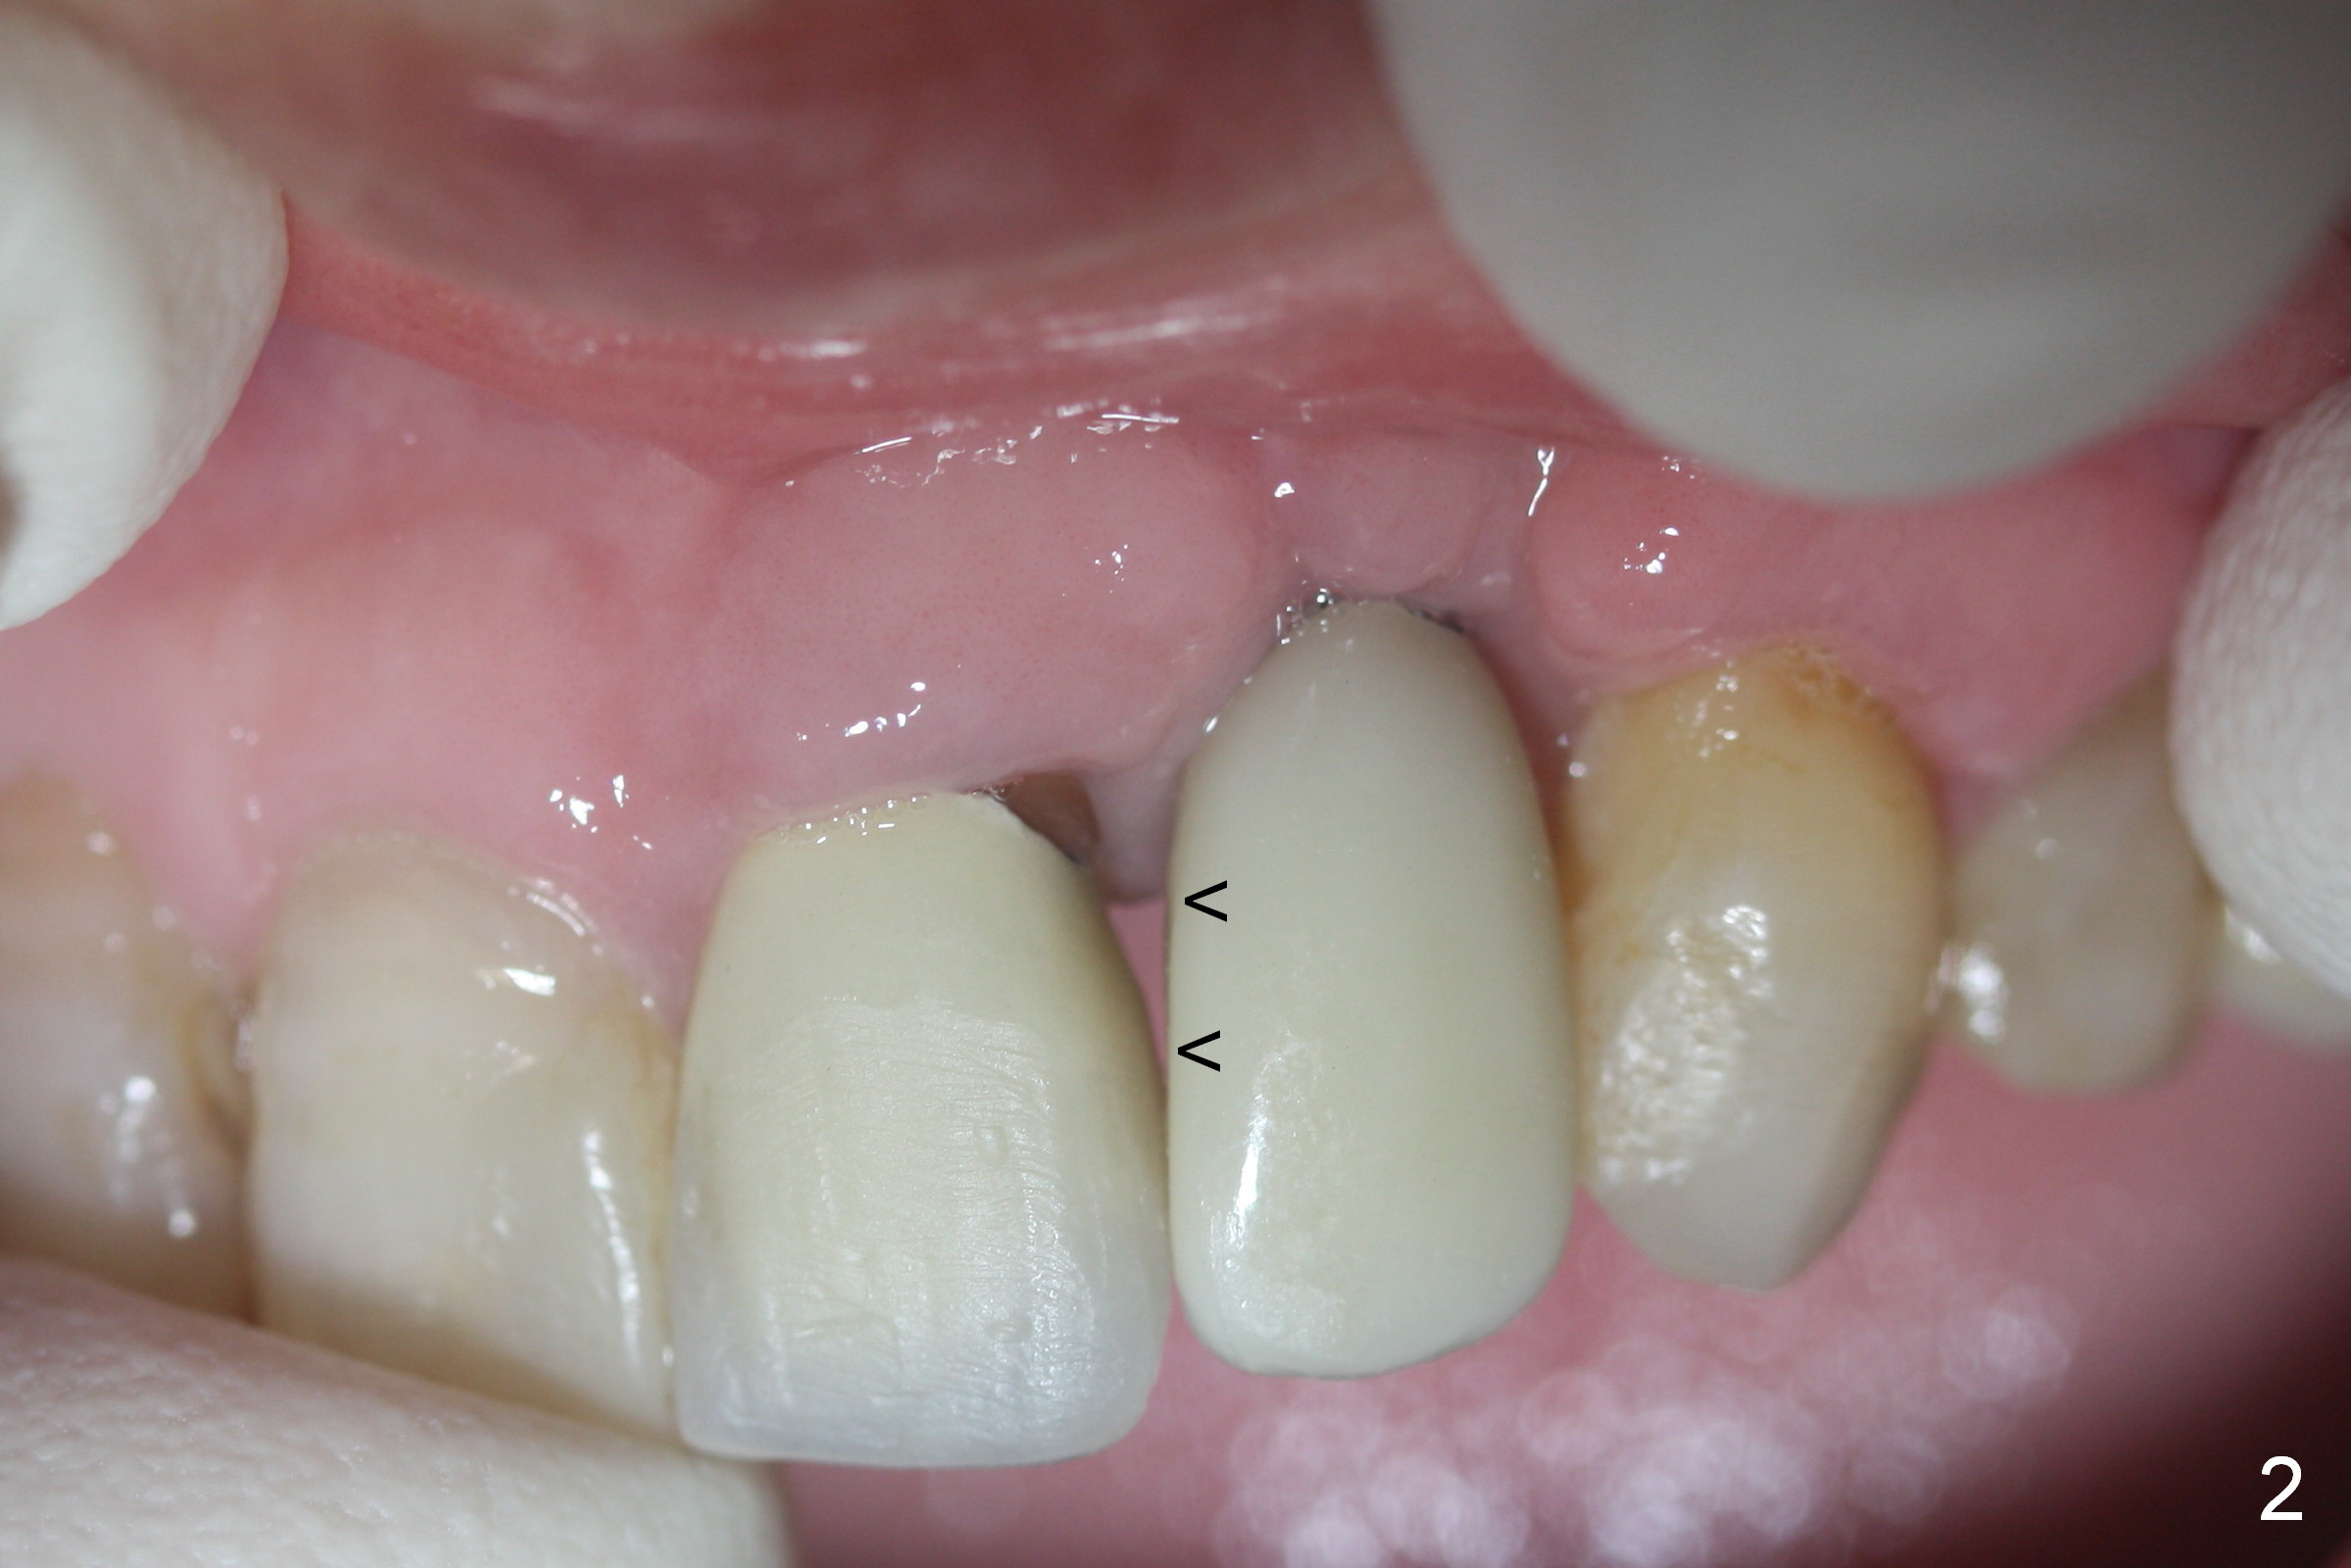

Mrs. Chen likes the shape of the temporary crown (Fig.1), particularly the mesial portion (arrowheads). Change the shape of the permanent crown (Fig.2 arrowheads) to alleviate the problem of papillary recession. Use the tooth #7 as a reference (Fig.3).